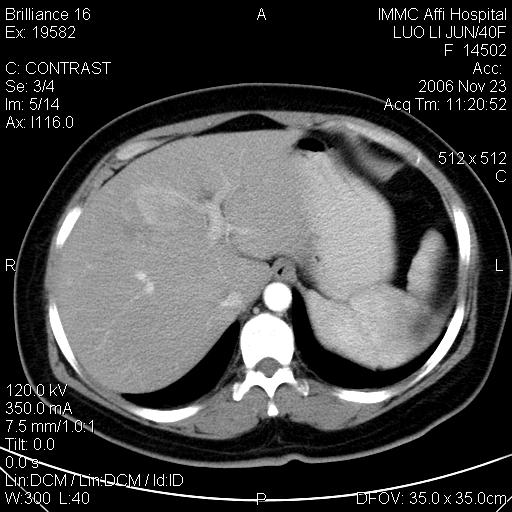

标题: CT5664:我也发一个肝脏的片子大家看看

很典型的肝癌。

速升速降,典型肝癌.

支持-----考虑肝癌----[-从片上看增强早期应该是动脉晚期即门脉早期]

是啊,典型的早出早归!

快进快出典型肝癌.

符合肝癌的增强特征。支持肝癌!

病灶好圆!可能恶性度不高。

不能除外肝细胞腺瘤吧,还是得结合病史。

很好的片子,可惜增强做的比较失败,a期时间没有把我好,实际到了静脉早期了,否则会更典型。

最终考虑是肝腺瘤